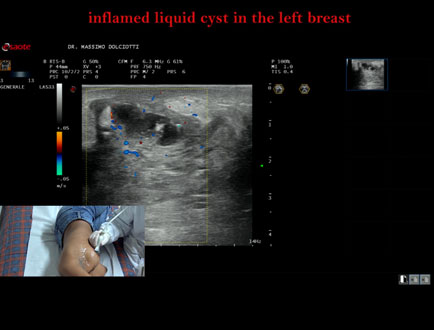

Data inserimento: 07/10/2025

Ecografia del: 15/05/2025

Strumento: Esaote MyLab Eight

Sonda: Lineare Multifrequenza 3-13 MHz

Età Paziente: F 16 anni

Motivazione dell'esame: da 2 giorni dolore alla mammella sinistra.

Commento all'esame: le immagini ed il video documentano al quadrante inferiore esterno ore 4 della mammella sinistra, formazione disomogenea ipoanecogena, delle dimensioni di 24 x 14 mm, da ricondurre a cisti liquida infiammata.

Conclusioni: cisti liquida flogosata alla mammella sinistra (inflamed liquid cyst in the left breast).

Presentazione: Dr. Massimo Dolciotti - Ancona